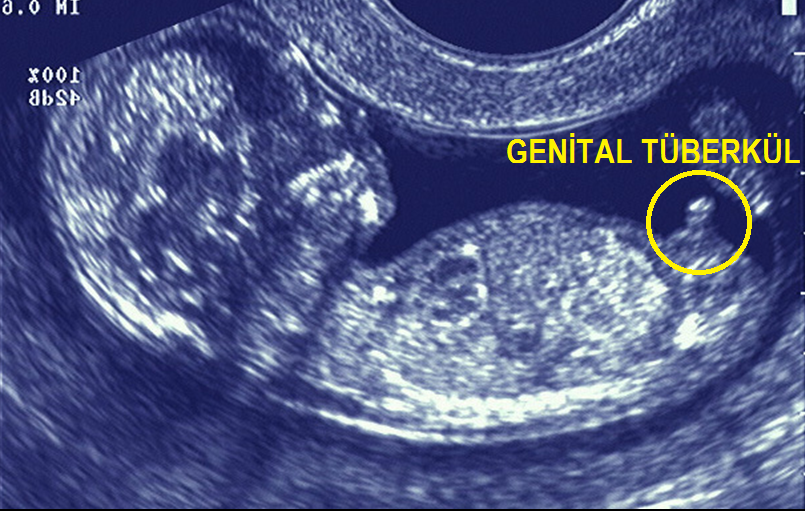

bebek cinsiyet hesaplama Hafta da belli olan gebelik çin takvimi ile ayrıca hesaplanmaktadır. Japon takvimi, tıpkı diğer cinsiyet hesaplama takvimleri gibi tamamen kültürel inançlarla şekillenen bir cinsiyet tahmin etme yöntemidir. Eğer %100 güvenilir bir sonuç elde etmek istiyorsanız. Persentil hesaplaması bebeklerin boy, kilo ve baş çevresi değerleri için ayrı ayrı yapılır. Günümüz şartlarında bu sorunun cevabı, ultrason görüntüsüyle 12. Eğer ocak ve mart aylarında hamile. Yani çin takvimi cinsiyet hesaplama da bebek cinsiyeti tahmin yöntemleri'nden yalnızca biridir. Şunu unutmayın ki, bilimsel değeri olmayan eğlenceli bir tahmin aracıdır.

2021 yılında da çin takvimi cinsiyet hesaplama gibi yöntemler popülerliğini koruyacak gibi görünüyor. 3.05.2022 · maya takvimi cinsiyet hesaplama otomatik. Günümüz şartlarında bu sorunun cevabı, ultrason görüntüsüyle 12.